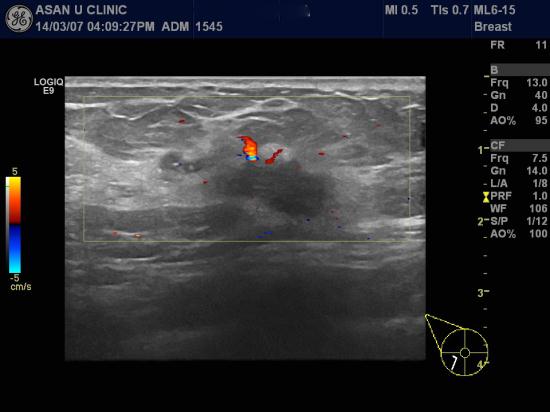

우측유방에 만져지는 몽우리있어

조직검사위해 의뢰된 44세 여성분입니다.

본원에서 시행한 초음파상

만져지는 부위 말고도

0.5cm의 유방병변과 우측 겨드랑이 림프절의 비대 있어

함께 조직검사 및 세포검사 시행하여

침윤성 유관암과 겨드랑이 림프절의 암전이 진단되었습니다.